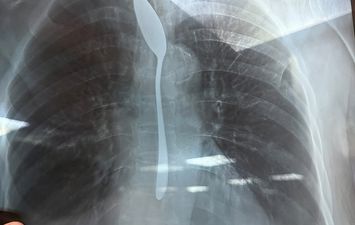

وبعمل الآشعه اللازمه أظهرت صورة واضحة لملعقة شاي كاملة مستقرة داخل المريء، مما استدعى تدخلا عاجلًا لإنقاذ حياتها.

وتم تجهيز المريضة داخل غرفة العمليات واستدعاء الاستشاري المختص، وتم استخراج الملعقة عن طريق منظار المريء في زمن قياسي لم يتجاوز من 5 إلى 7 دقائق، وسط حالة من الترقب داخل غرفة العمليات، وتمت العملية بنجاح كامل دون أي مضاعفات.